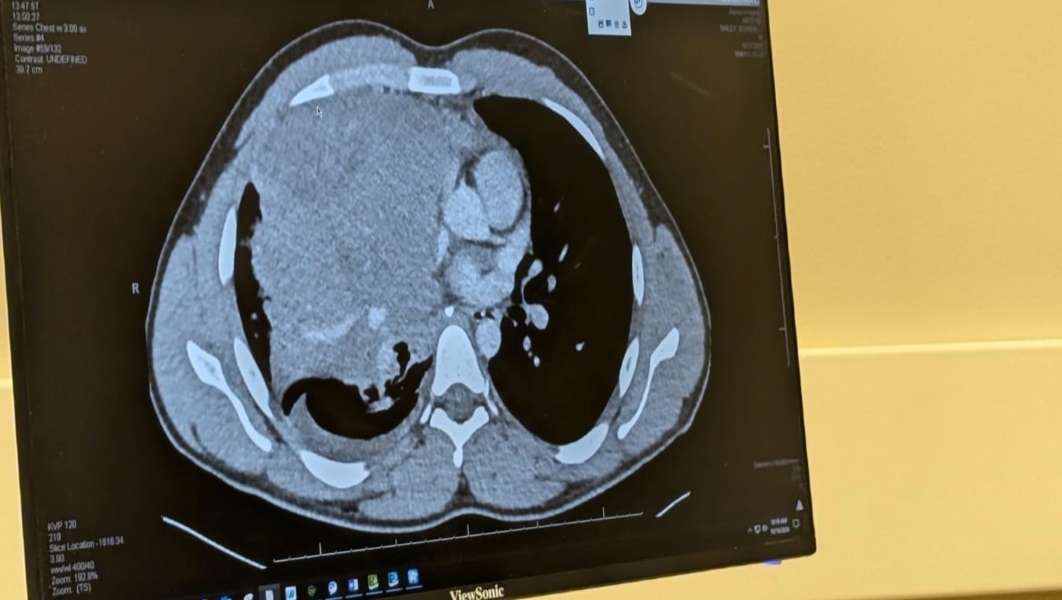

Doctors initially thought Bailey had pneumonia or tuberculosis, but after performing an X-ray and CT scan, they found a cantaloupe-sized mass in the middle of his chest. Elder Bailey's mission would suddenly come to an end as he was rushed home to eastern Idaho for life-saving treatment.

The massive tumor is uncomfortable — pressing his right lung tight against his chest to the point "you can just barely see the lining of my lung where (the tumor)'s pushing so big," he explains.

"It's growing in the lymphatic system," says Jon Bailey, Bowen Bailey's father. "Imagine this big, massive mass, probably smaller than a volleyball but a very large cantaloupe, and it's basically pushing his lung all the way to his ribs, so that there's no use of that lung."

Upon returning home, Dr. Tom Jones of Teton Medical Group immediately performed another biopsy, which determined that the tumor was growing outside of Bowen's lung. Bowen was diagnosed with nodular sclerosis Hodgkin lymphoma.

Because the tumor is wrapped around so many vital organs, it cannot be removed surgically, but doctors strongly recommended chemotherapy to treat the cancer.